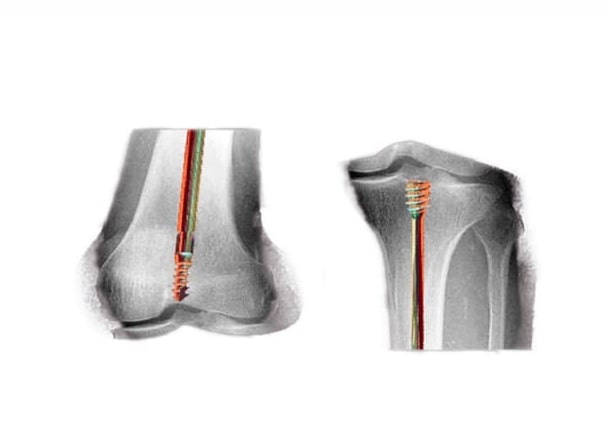

“Vino en un coche de bebé y se le práctico un tratamiento con un clavo especial, un clavo telescopado para corregir la deformidad, que se ancla en zonas seguras del hueso. Se calcula dónde tiene que ir cierto corte del hueso para recuperar el eje normal del cuerpo. El chico crece con el clavo y el clavo se elonga a medida que el chico crece”, describió.

Es importante, no obstante, el control permanente del clavo telescopado “hasta que cumpla la mayoría de edad ósea, cuando termina el crecimiento, que varía entre el hombre y la mujer”, subrayó Garabito.